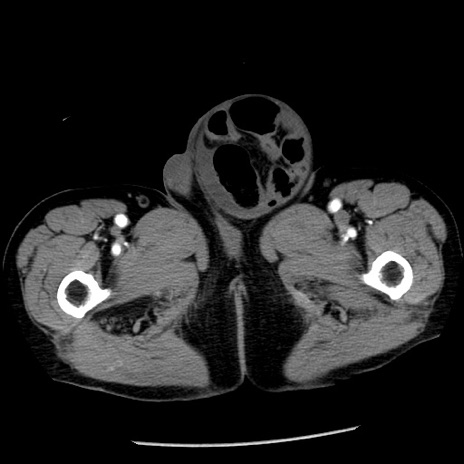

冠状断像